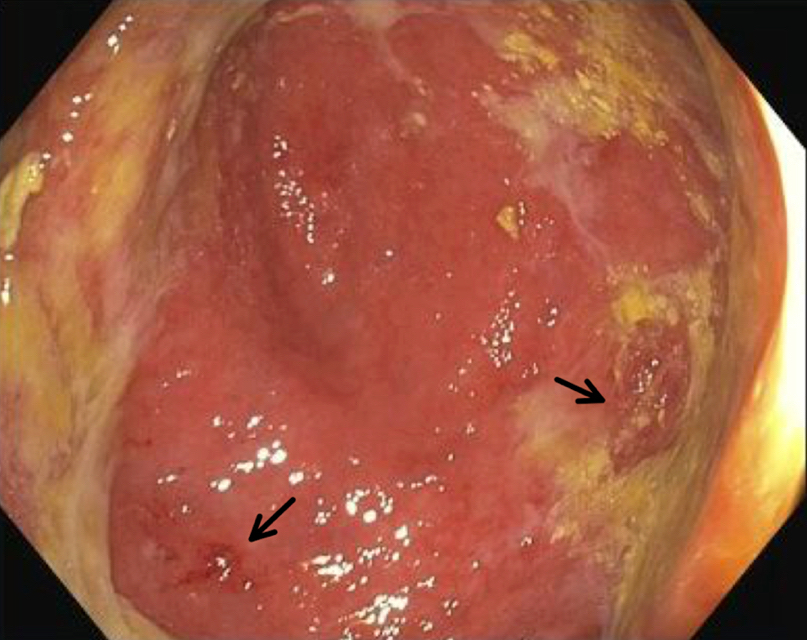

- Endoscopic findings range from edema and mild erythema to mucosal erosions, ulceration and denudation (Nat Rev Gastroenterol Hepatol 2017;14:711)

Microscopic (histologic) images